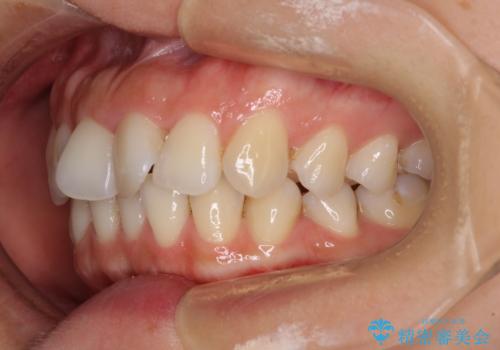

- 捻れた前歯が飛び出しており、口が閉じにくいとのことで来院された患者様です。

出っ歯というわけではないものの、前歯の捻転により口唇が押し出されている状態でした。

親知らずを抜去し、歯列全体を後方に移動させつつ、IPR(歯と歯の間を削る)でスペースを獲得し、インビザラインを用いて叢生を解消しながら前歯の突出を改善することとしました。

骨格的に上下正中がずれていたため、奥歯がしっかりと噛み合うか心配でしたが、ずれているなりに、しっかりとした咬み合わせとなりました。